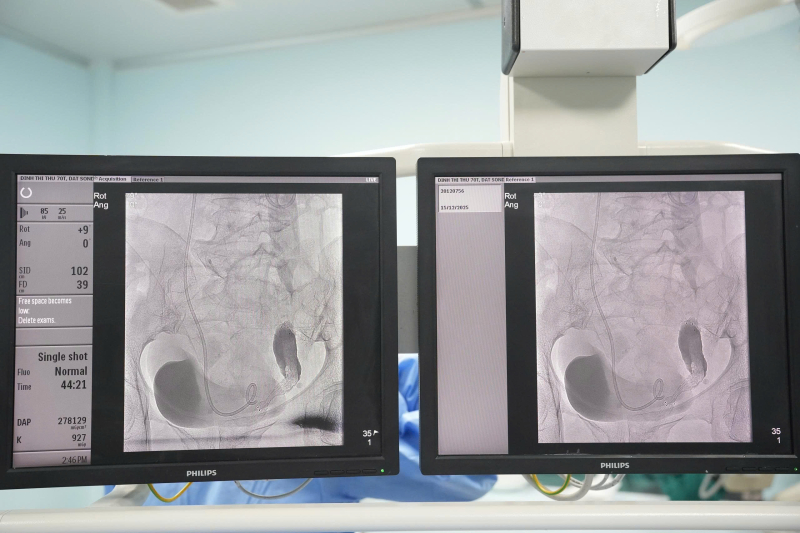

Bệnh viện Bãi Cháy triển khai kỹ thuật đặt stent niệu quản và sonde JJ bể thận – bàng quang qua da dưới hướng dẫn của DSA

Bệnh viện Bãi Cháy vừa triển khai thành công kỹ thuật đặt stent niệu quản và sonde JJ bể thận – bàng quang qua da dưới hướng dẫn của hệ thống chụp mạch số hóa xóa nền (DSA), đánh dấu bước tiến quan trọng trong ứng dụng các kỹ thuật can thiệp xâm lấn tối thiểu trong điều trị bệnh lý tiết niệu.

Hình ảnh: stent niệu quản trên hệ thống chụp mạch số hóa xóa nền (DSA).